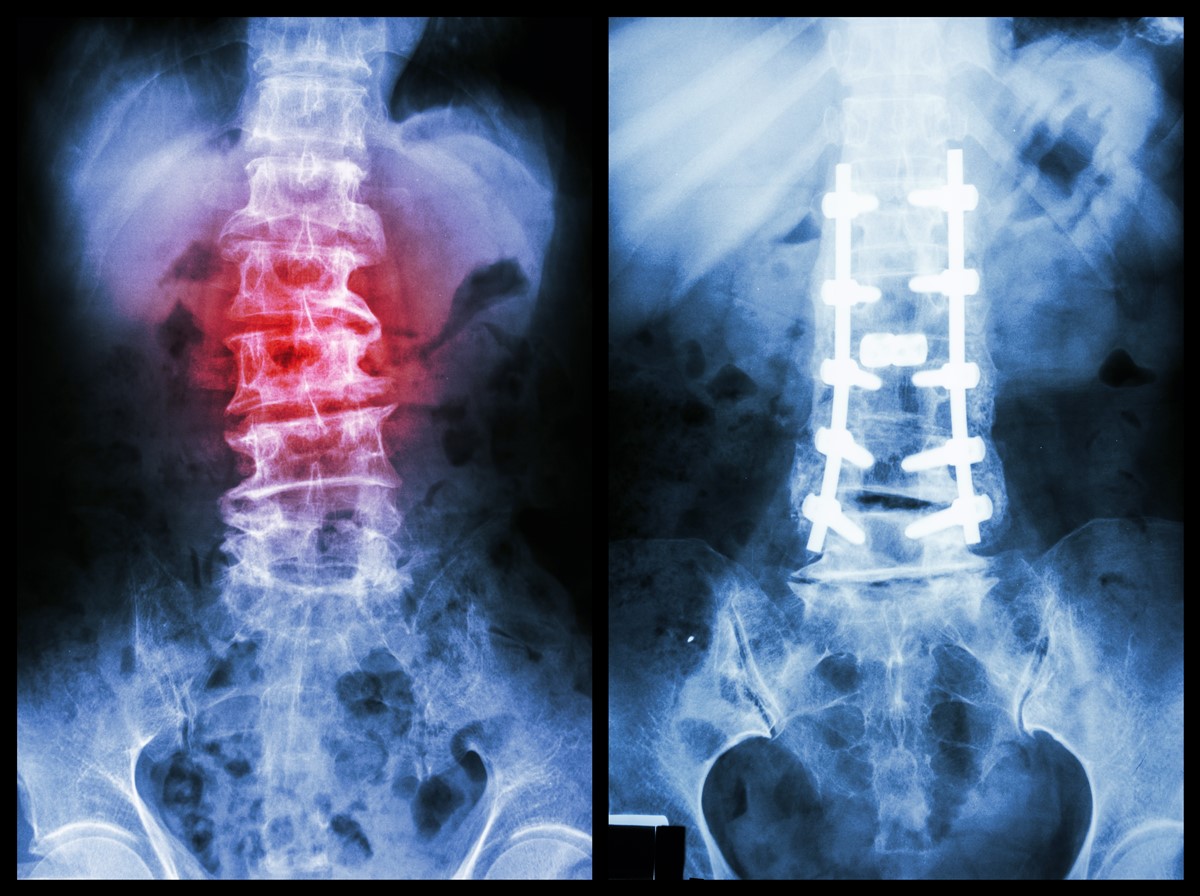

Surgical treatment aims at decompressing the nerves and stabilizing the spine to prevent a recurrence of the condition. In a lot of the cases, the amount of mobility at the level of the slip is much that a fusion surgery will have to be considered.

A fusion surgery is done most commonly at the L5-S1 since the incidence of spondylolisthesis is highest here. Interestingly, since this segment lies pretty deep in the pelvis and is not really designed for a lot of motion, patients do not really feel too much of limitation to their movement once the procedure has been performed.